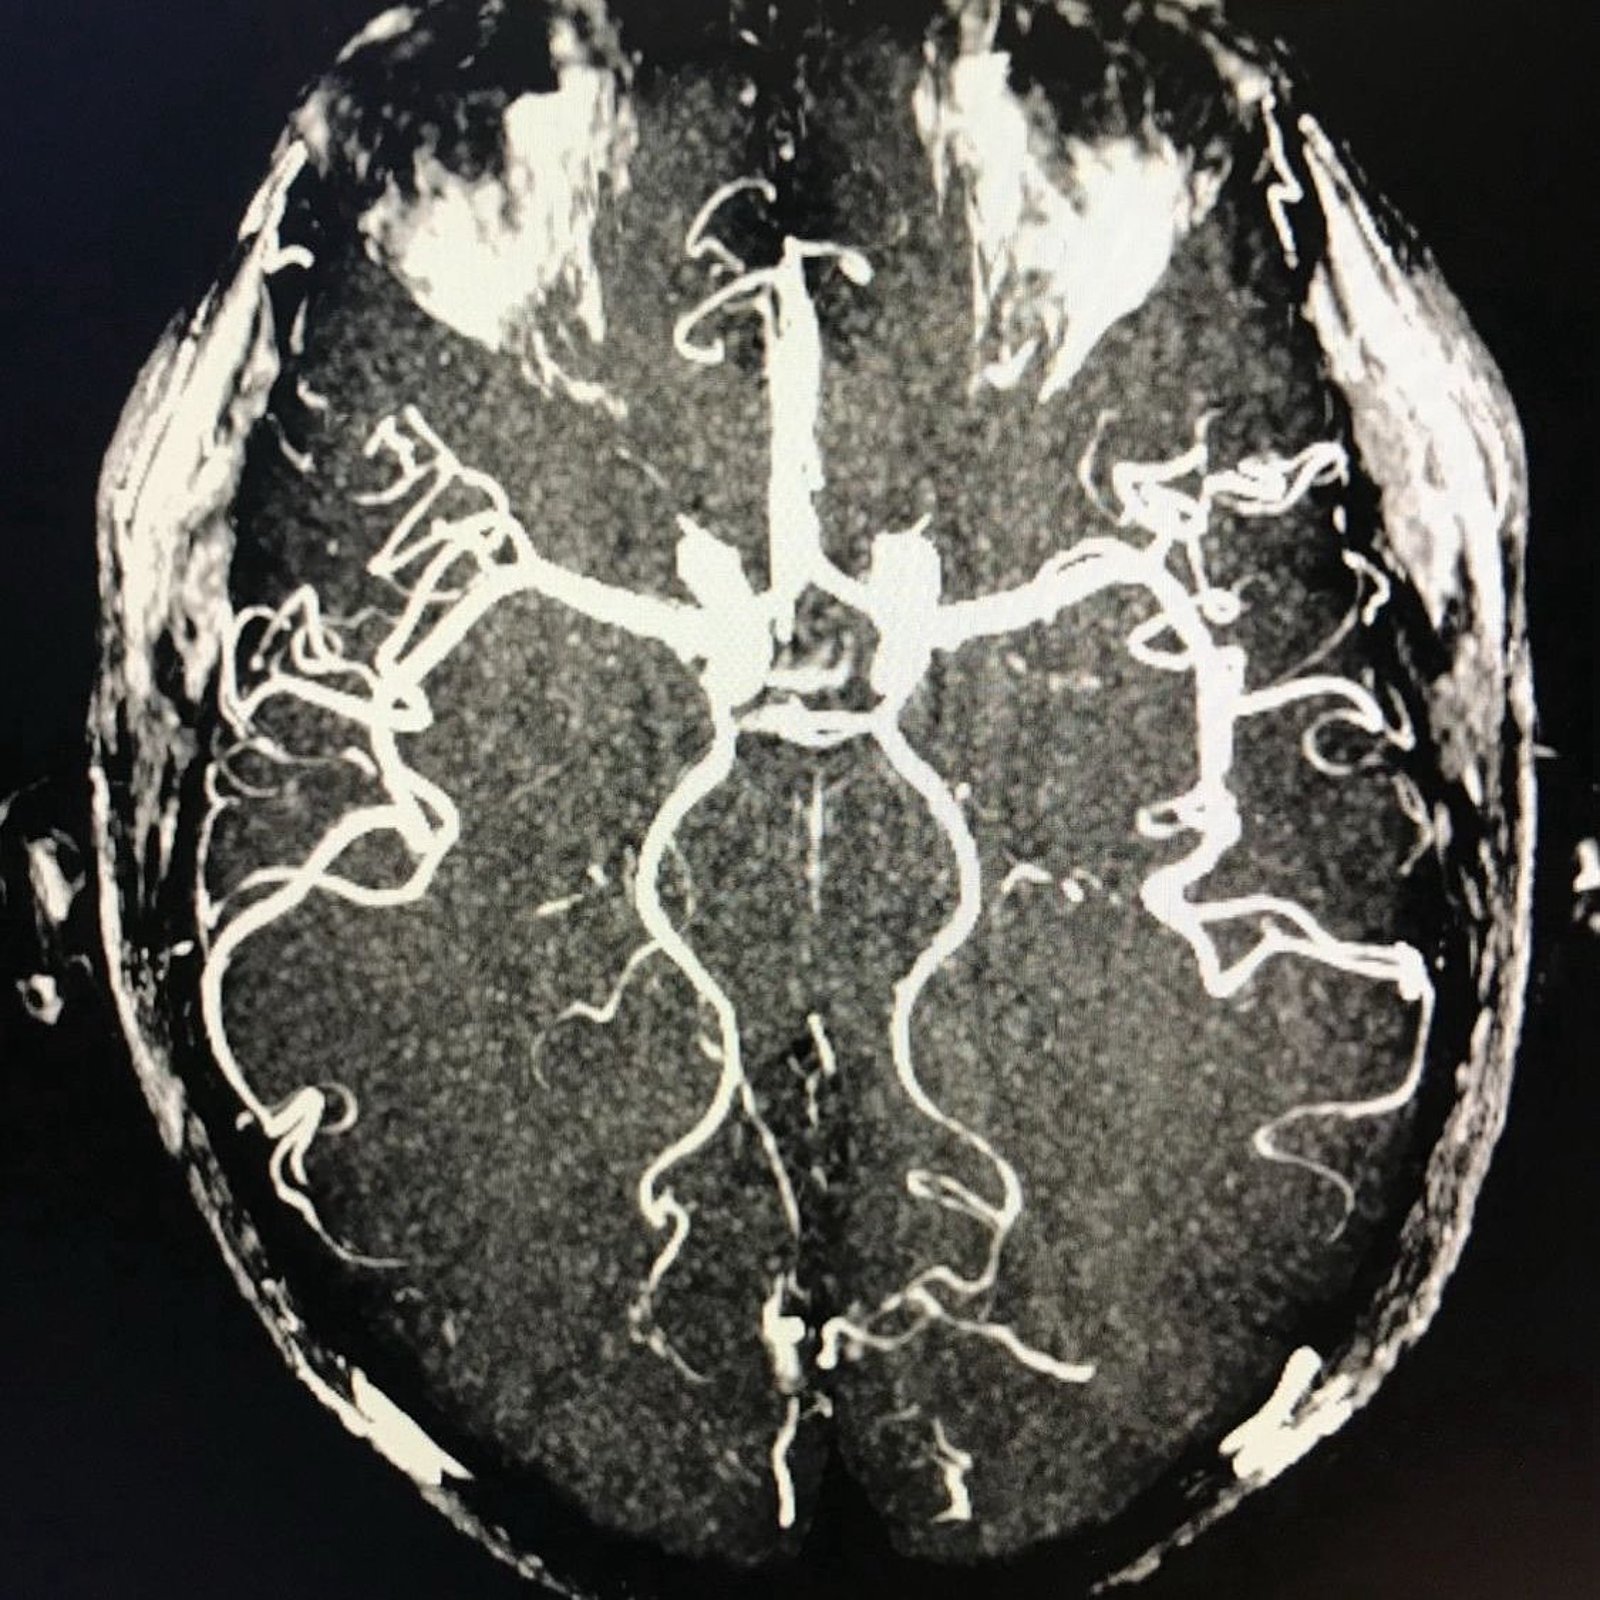

Die Diagnose brachte dann endlich Klarheit. Glücklicherweise zeigten die Untersuchungen meiner Blutgefäße (s.Bild), dass sie frei von Plaques waren, was mir eine große Erleichterung und Hoffnung für die Zukunft gab. Mein Neurologe ermutigte mich eindringlich, ohne Angst an die Genesung zu denken und positiv nach vorne zu blicken.